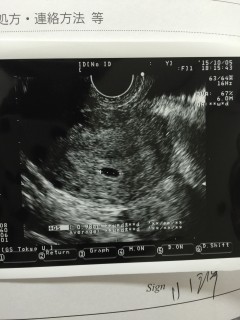

この日の前日に別の病院では、胎嚢の大きさは5mmで平均より小さいですね、周期もまだわからない。と言われました。 なんだか業務的で不安だったので、翌日他の病院に行った時のエコー写真です。 前日は5mmだったのが、なんと9.4mmありました。 二週間後にまた検診です(^^) 胎芽と心拍が確認出来るといいな♪